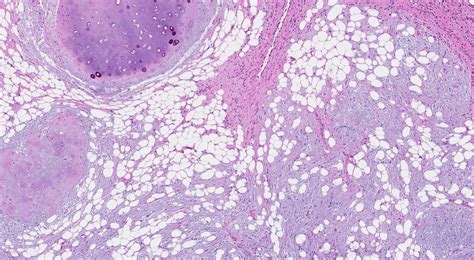

Hamartoma sudaryta iš netvarkingai išsidėsčiusių normalaus audinio komponentų - mezenchimos, bronchų sienos ir plaučių parenchimos audinių elementų. Mikroskopuojant matoma, kad navikas sudarytas iš jungiamojo audinio, kremzlių fragmentų, riebalų, kartais - lygiųjų raumenų ir kaulinio audinio fragmentų. Pagal vyraujantį audinį skiriama hamartochondroma, fibrohamartoma, lipohamartoma ir kt. Hamartomą dengia neneoplazinis respiracinis epitelis.